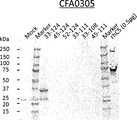

- Figure 5A illustrates Western Blot analysis against MG1-MG2 domain-derived peptide fragments (amino acids 33-124, 45-124, 52-124, 33-111, 33-108, and 45-111 of SEQ ID NO:40) fused to GST-tag, as described in Example 4.4.

- Anti-GST antibody is used as an antibody for reaction.

- the position of the GST-fused C5 fragments (35-37kDa) is marked with an arrow.

- Figure 5B illustrates Western Blot analysis against MG1-MG2 domain-derived peptide fragments (amino acids 33-124, 45-124, 52-124, 33-111, 33-108, and 45-111 of SEQ ID NO:40) fused to GST-tag, as described in Example 4.4.

- CFA0305 is used as an antibody for reaction.

- Figure 5C summarizes binding reactions of anti-C5 antibodies to C5 beta-chain-derived fragments, as described in Example 4.4.

- the fragments to which the anti-C5 antibodies grouped into epitope C (CFA0305, CFA0307, CFA0366, CFA0501, CFA0538, CFA0599, CFA0666, CFA0672, and CFA0675) bind are shown in gray, and the fragments to which they don't bind are shown in white.